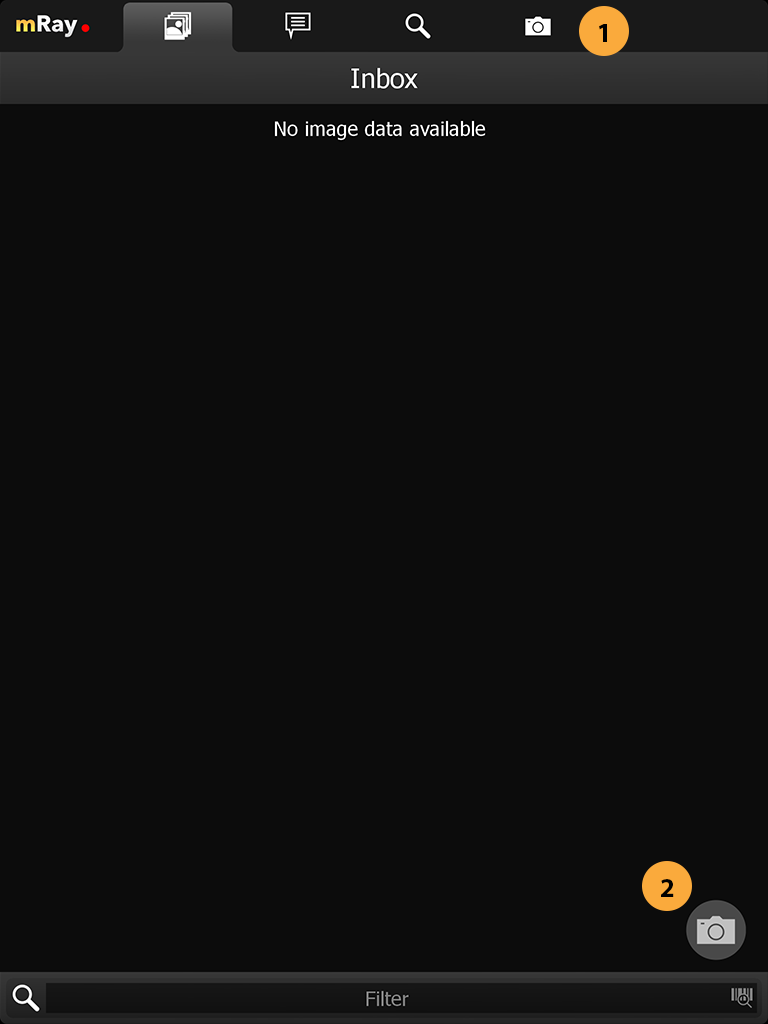

15. Photo documentation

|

The photo documentation feature is expressly not permitted for diagnosis or treatment decisions. This feature isn’t enabled by default. It is only available for evaluation purposes. If you’re interested in taking part of the evaluation, please contact your mbits support staff. |

When the feature is enabled for the current user you’ll see an extra tab for the photo documentation and a button in your inbox to open the camera. By pressing on the camera button (Point 2) you’ll open the camera and be able to capture all the photos you require. A photo documentation workflow will be like the following

Go to the Photo documentation tab

-

Open the Photo documentation camera